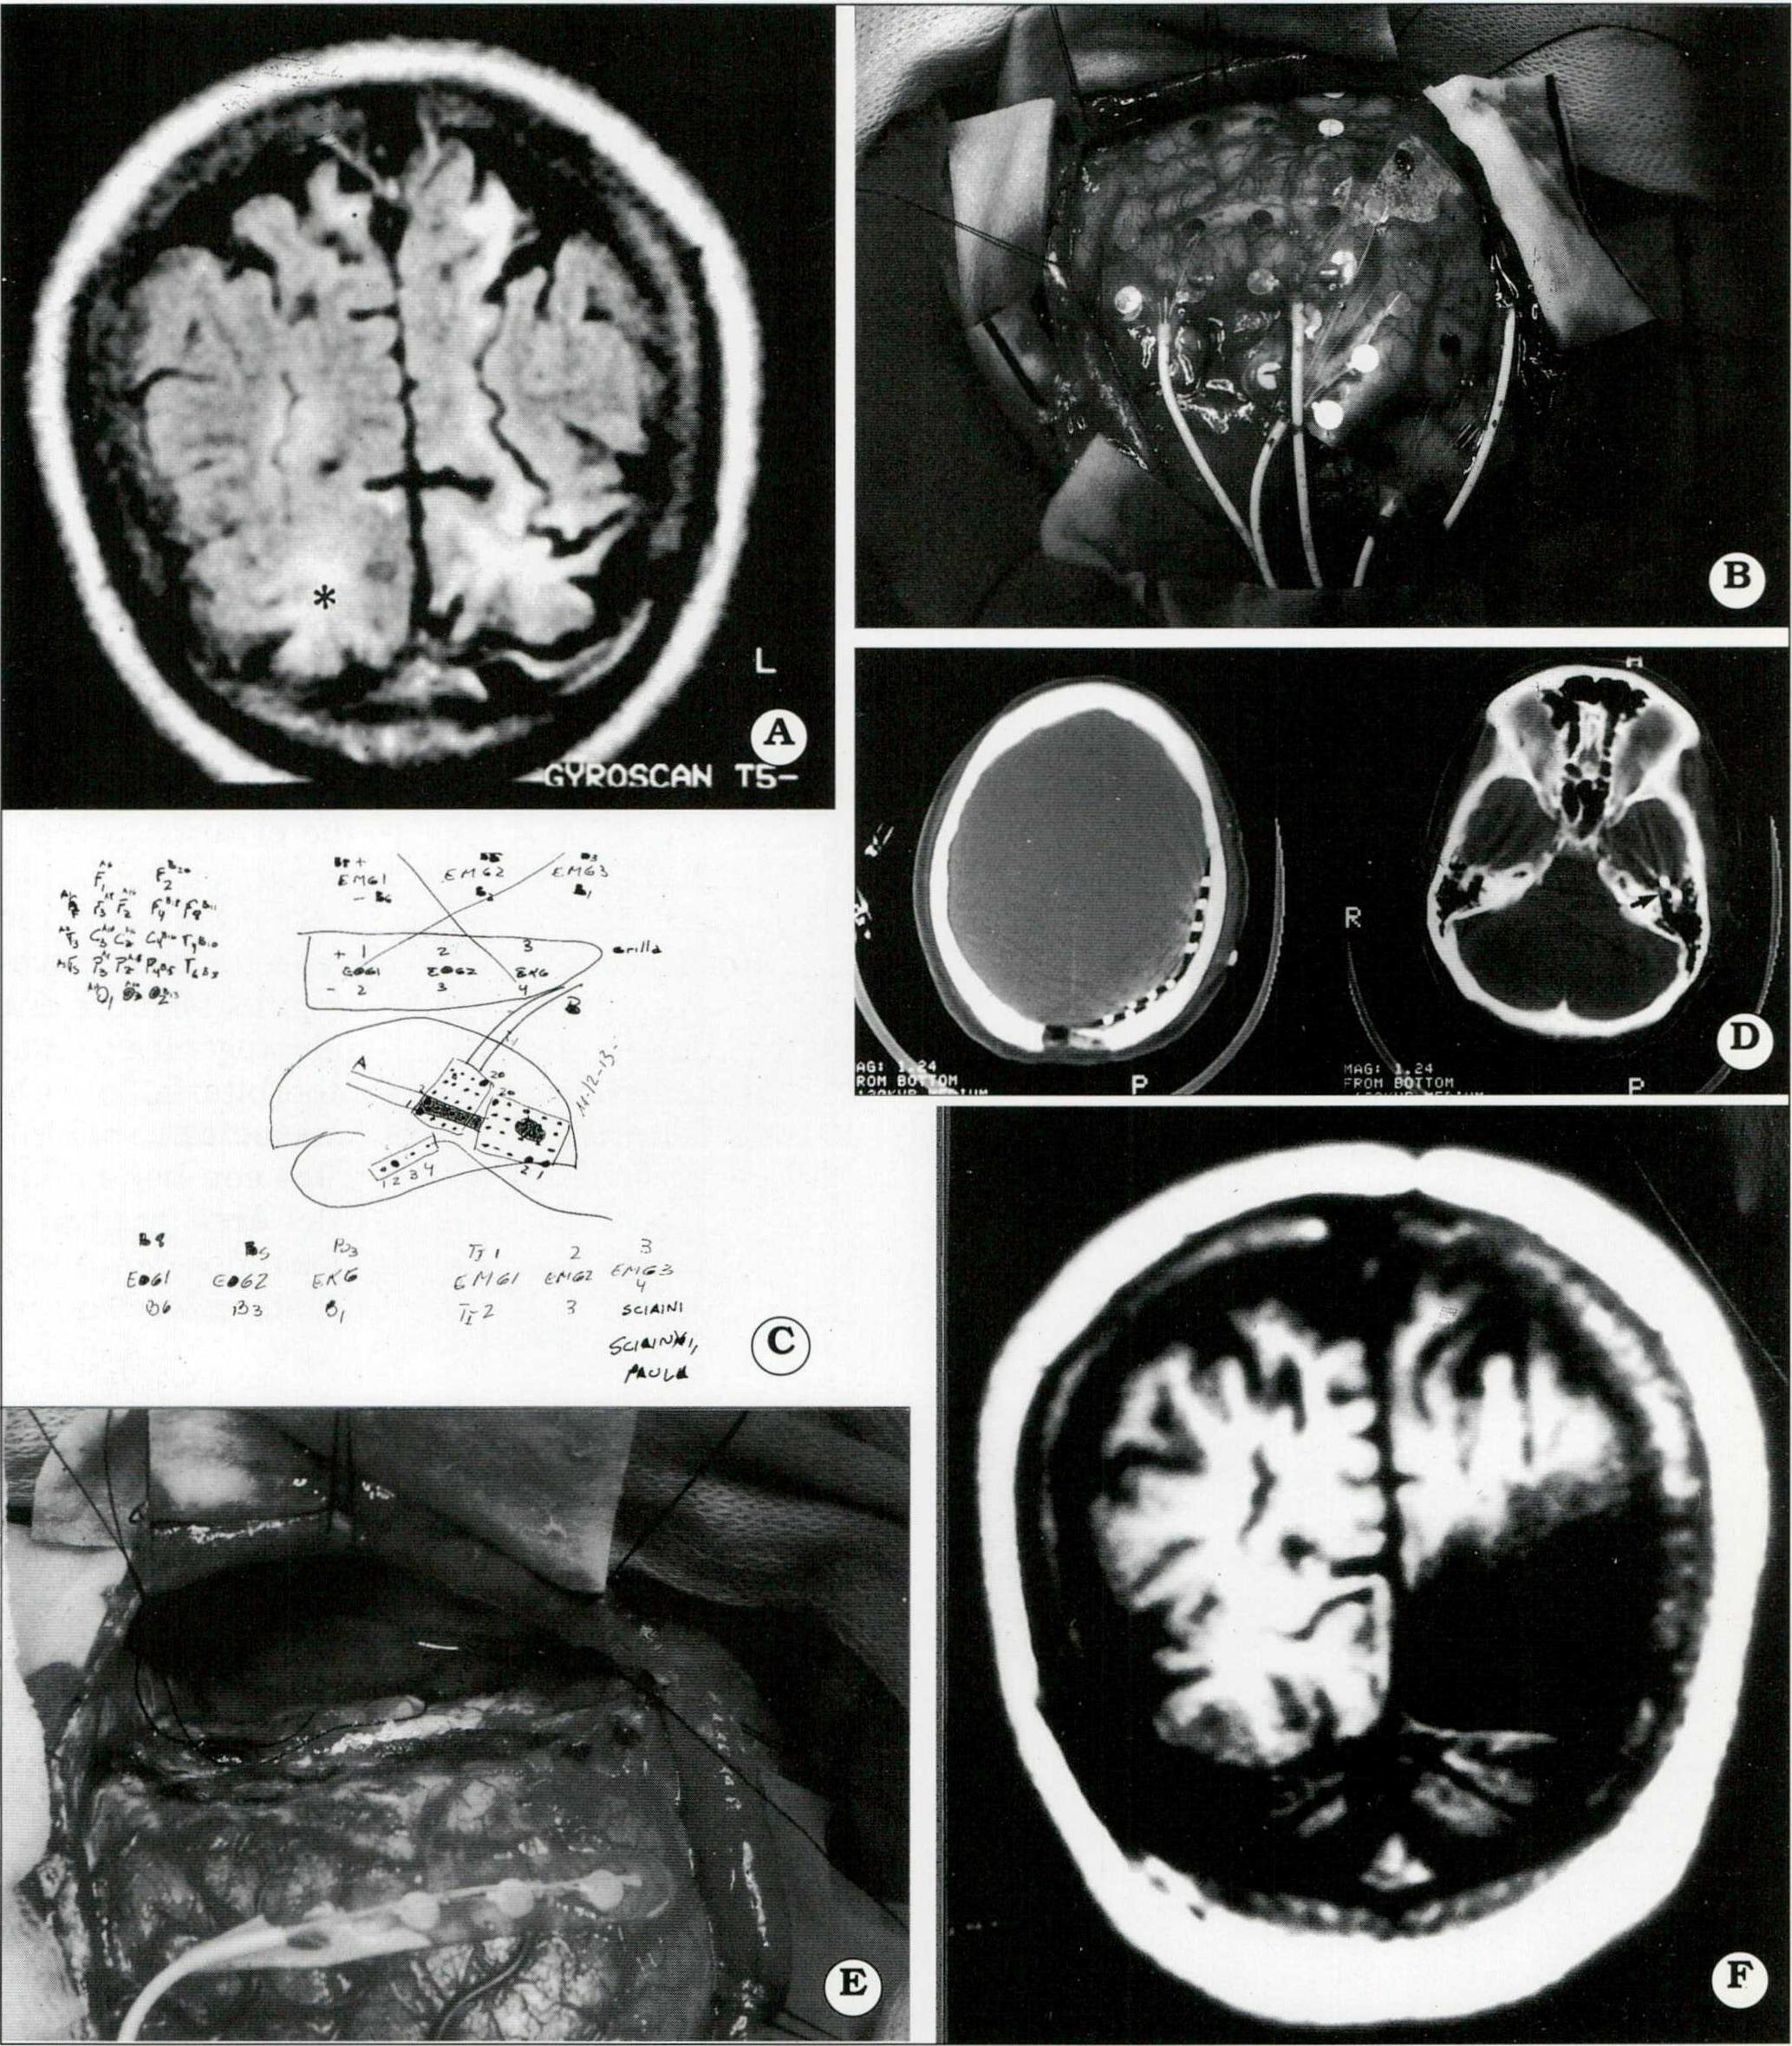

Fig . 4. A. IRM preoperatoria que muestra una lesión occipital, hiperintensa en T I (estrella). B. Colocación de 2 plaquetas de 20 electrodos subdurales parietooccipitales. C. Esquema intraoperatorio, orientador para el trabajo del equipo de neurofisiología, durante la videotelemetría con los electrodos implantados. D. TAC con ventana ósea. Muestra la ubicación de los electrodos parieto-occipitales y en la base del lóbulo temporal (a la derecha, flecha). E. Polectomía occipital derecha. F. IRM postoperatoria.